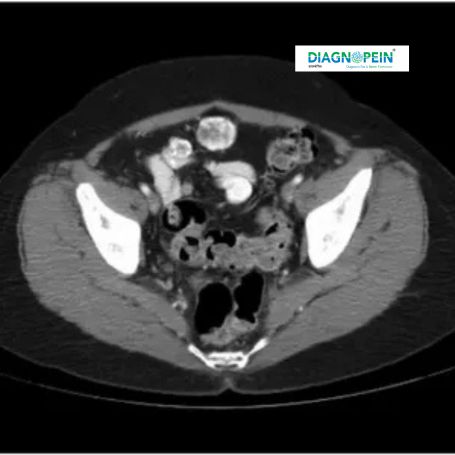

CT Pelvis Contrast scan is an advanced imaging procedure used to examine organs, blood vessels, and tissues in the pelvic region with enhanced clarity. The "contrast" refers to a special dye injected into the bloodstream that highlights internal structures during imaging, making abnormalities like tumors, infections, or injuries easier to detect.

At Diagnopein Nashik, modern multi-slice CT scanners and expert radiologists ensure precise imaging of the pelvic region for fast and accurate diagnosis. This scan is commonly advised for evaluating pelvic pain, trauma, cancer spread, or inflammatory conditions affecting the bladder, uterus, ovaries, prostate, or intestines.

The patient lies flat on a CT scanner table. The contrast dye is administered intravenously while the scanner rotates to capture detailed cross-sectional images of the pelvic area. The placement and scan angles are adjusted precisely to focus on target organs like the urinary bladder, reproductive organs, and lower intestines.